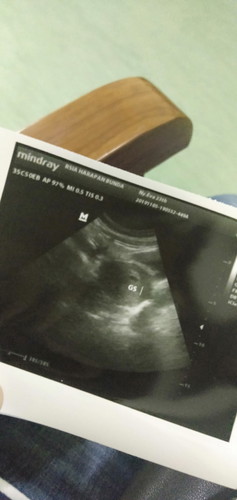

MasyaAllah 3 tahun menanti tnpa diduga teryata positif hamil.?? sekarang usia 6minggu.